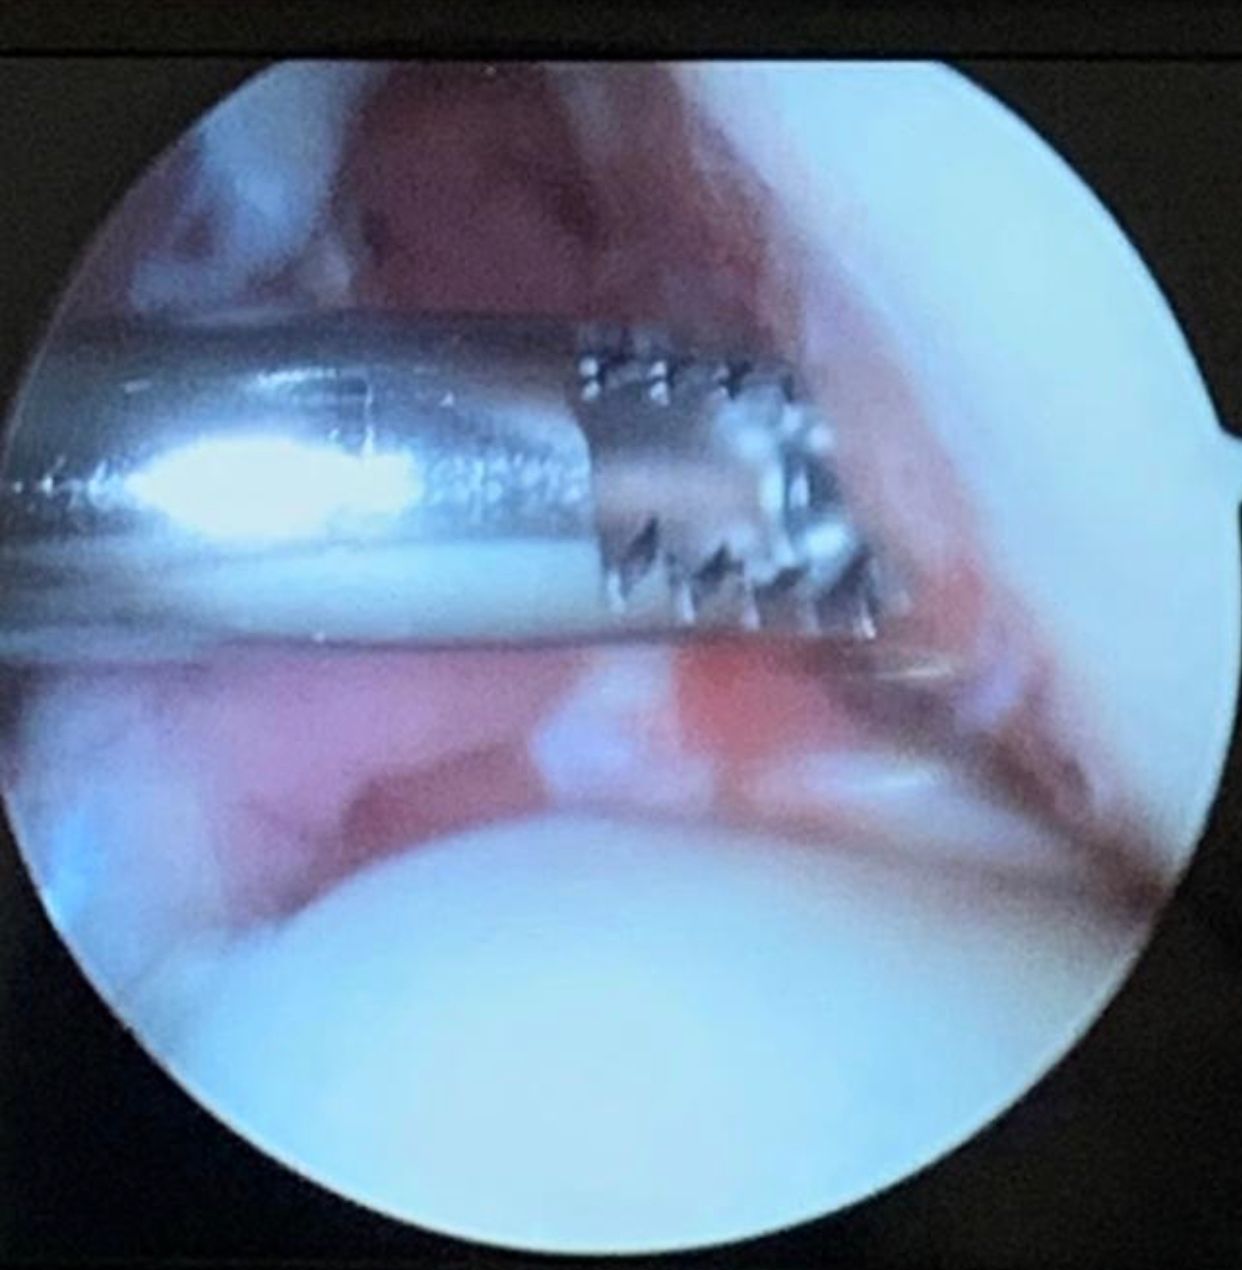

• Cirurgia do Joelho

• Cirurgia robótica

Artroscopia Cirurgica Do Joelho individualmente

Videoartroscopia individualmente

Reconstrução ligamentar intra-articular do joelho (Ligamentoplastia) individualmente

Artroscopia individualmente